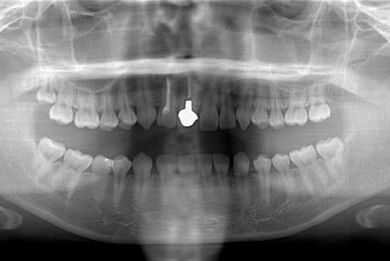

| 性別/年齢 | 女性 / 21歳 | ||||||||||||||||||||||||||||||||

| 主訴 | 歯の変色、欠けた部分を治したい。 | ||||||||||||||||||||||||||||||||

| 治療方針 | 上前歯を根管治療後、オールセラミッククラウンにて審美的回復を行う。 | ||||||||||||||||||||||||||||||||

| 治療内容 | オールセラミッククラウン2本(オールセラミック用土台2本) | ||||||||||||||||||||||||||||||||